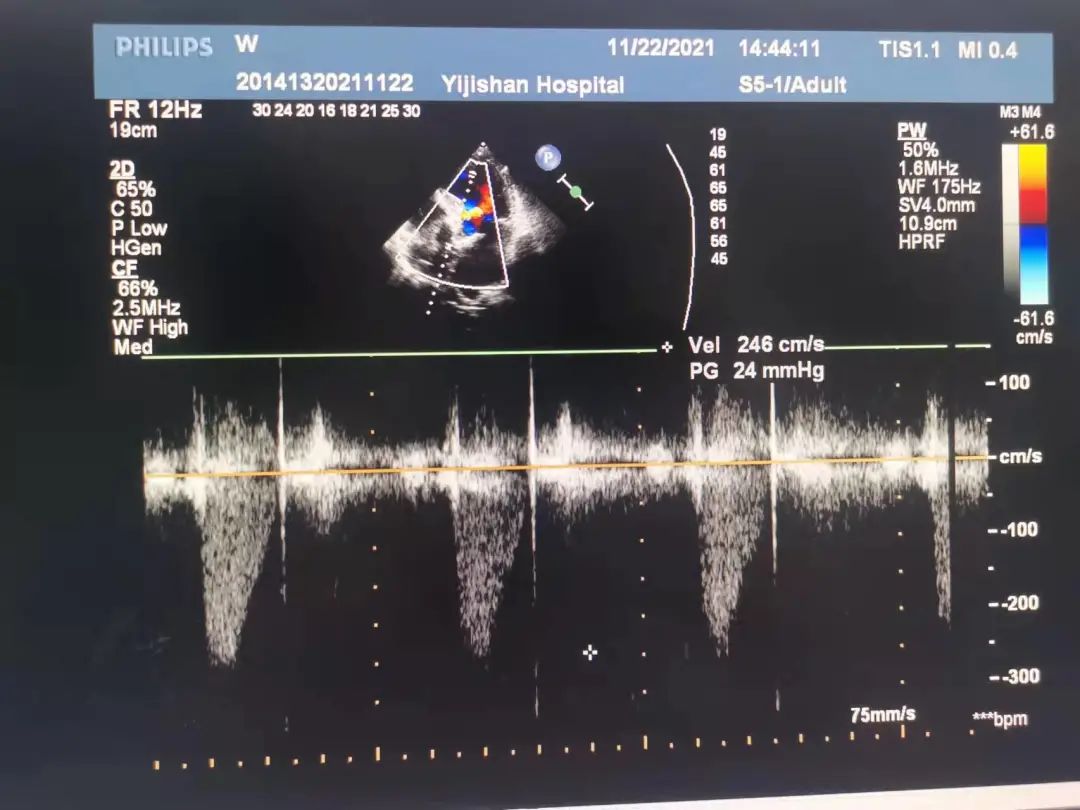

心脏彩超示:升主动脉硬化并增宽,左房增大;主动脉瓣钙化伴重度狭窄,轻度反流。

最高跨瓣压差:123mmHg;

左室舒张末期内径(LVD):4.9cm。

术后经心尖超声